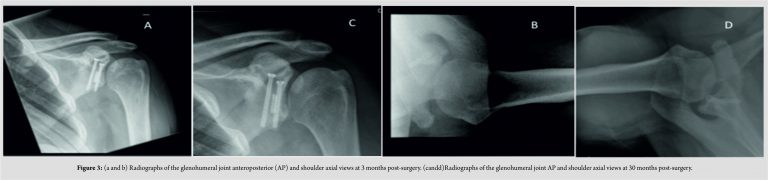

Follow-up of the patient at 3, 6, 12, 24, and 30 months was performed. Functional outcomes scores including constant score, Oxford shoulder, and disability of the arm, shoulder, and hand (DASH) were performed. Radiographs at 3 months and 30 months are shown in Fig. 3. Table 1 summarizes the functional scores over time, which has shown significant improvement during the post-operative period. In the case of negative correlations, this showed that reductions in the difference in DASH scores between shoulders occurred over time, indicating a return of normal function. Currently, the patients have returned to work as a manual shop assistant, plays rugby and cricket, with no pain, functional limitation, or restriction on activities of daily living.